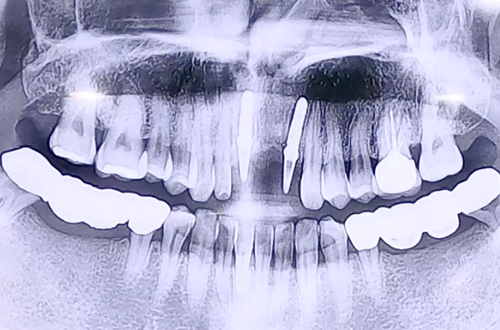

BEFORE

일요일에 앞니에 진행한 보철이 떨어지면서 급하게 내원해 주신 환자분이십니다.

기존에 진행한 브릿지가 걸려 있던 양 옆의 치아들이 충치에 의해 약해지며 보철이 빠지셨어요.

치아 상태를 살펴보니 충치에 의해 치아가 많이 상하고 변성이 심하게 되어 있어 보철치료로 남아 있는 자연 치아를 살릴 수 없고, 만약 보철치료를 한다 해도

안쪽까지 진행된 충치로 예후가 좋지 않을 것으로 보아 당일 발치 후 즉시 임플란트를 진행하였습니다.

다행히 잇몸뼈는 단단하고 건강하셨기 때문에 발치 후 임플란트를 단단히 심을 수 있었습니다.

앞니이기 때문에 임시치아를 제작하고 보철 부품을 끼워 마무리해 드렸습니다.